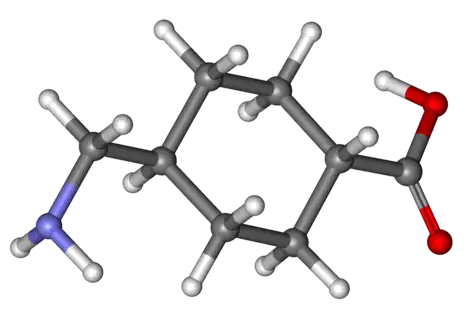

In terms of haemophilia C medication tranexamic acid is often used for both treatment after an incident of bleeding and as a preventive measure to avoid excessive bleeding during oral surgery.[3]

Treatment is usually not necessary, except in relation to operations, leading to many of those having the condition not being aware of it. In these cases, fresh frozen plasma or recombinant factor XI may be used, but only if necessary.[4][10]

Cyklokapron (Tranexamic acid)

Cyklokapron (Tranexamic acid) Fresh Frozen Plasma